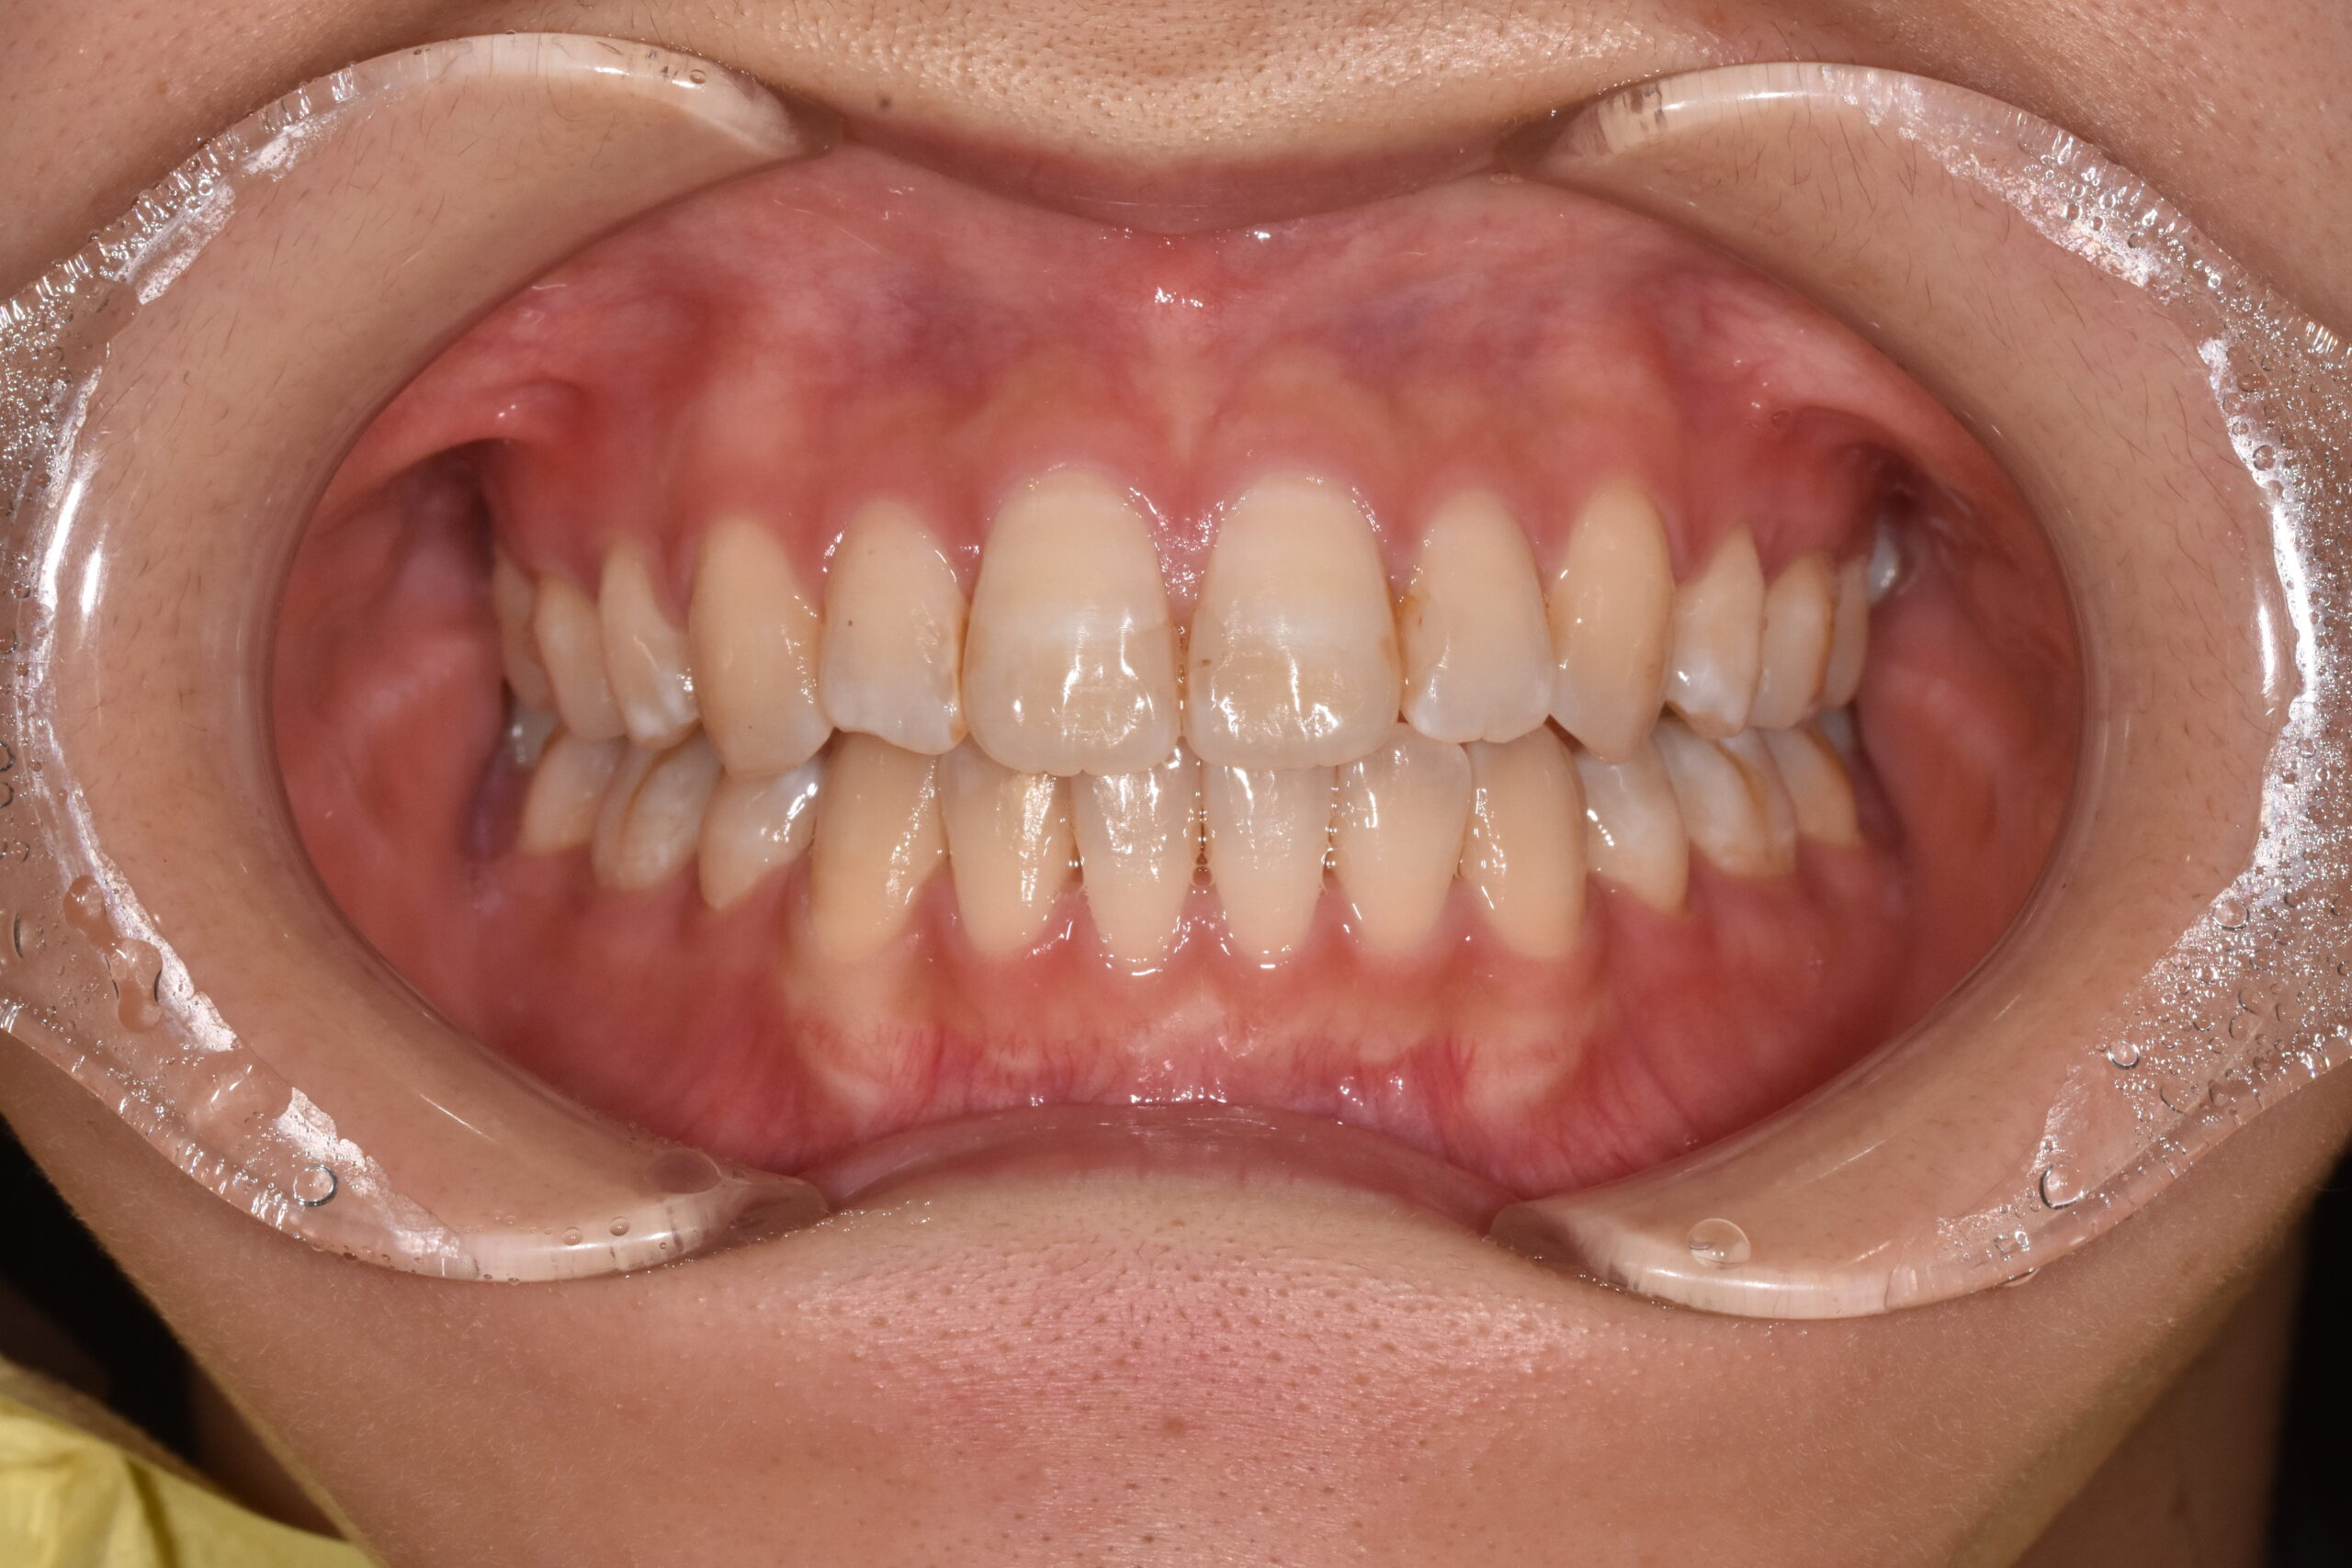

治療後

治療方法:

上下左右の第1小臼歯(4番)を抜歯し、マウスピース型矯正装置を用いて歯並びとかみ合わせの改善を行いました

治療のポイント:

・抜歯によりスペースを確保し、前歯の位置と角度をコントロール

・マウスピース矯正により、見た目と快適さに配慮しながら治療

・奥歯の高さを調整し、前歯がしっかり噛むように改善

・舌のクセ(舌突出癖)にも配慮し、後戻りを予防